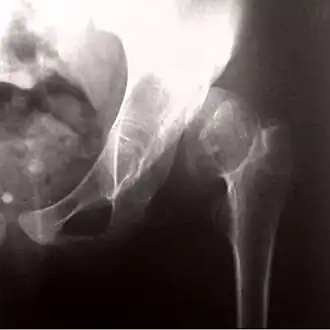

![]() Рентгенограмма, демонстрирующая развитие псевдоартроза при врожденном вывихе бедра | |

Врожденный вывих бедра также может стать причиной возникновения псевдоартроза.

Диагноз ставится на основании рентгеновских снимков в двух взаимно перпендикулярных проекциях и клинических проявлений.